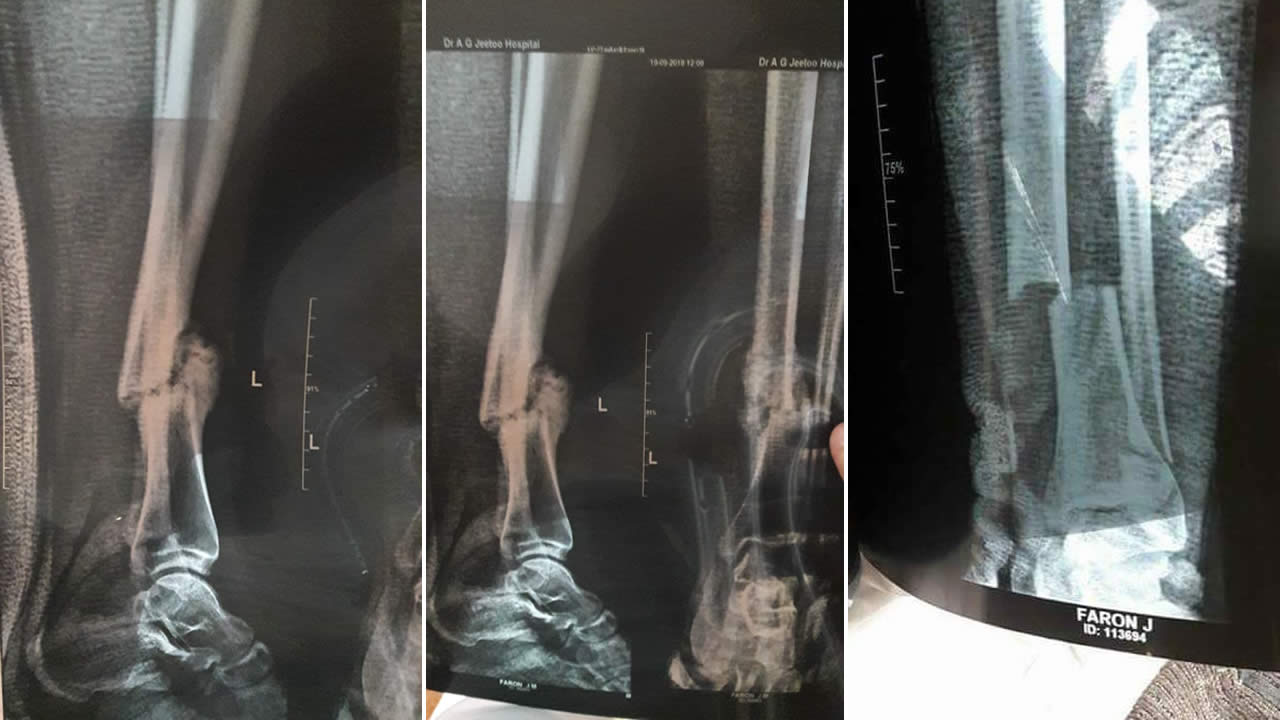

Une semaine après, il entre dans le bloc opératoire mais il en ressort… plâtré ! On lui enlève le plâtre en avril et son médecin traitant lui prescrit des séances de physiothérapie. Cependant, dit-il, son état ne s’est pas amélioré et c’est à travers un X-Ray qu’on découvre que son pied est toujours fracturé et qu’aucune vis n’y a été posée. « Je ne comprends pas pourquoi on m’a emmené en salle d’opération », lance-t-il.